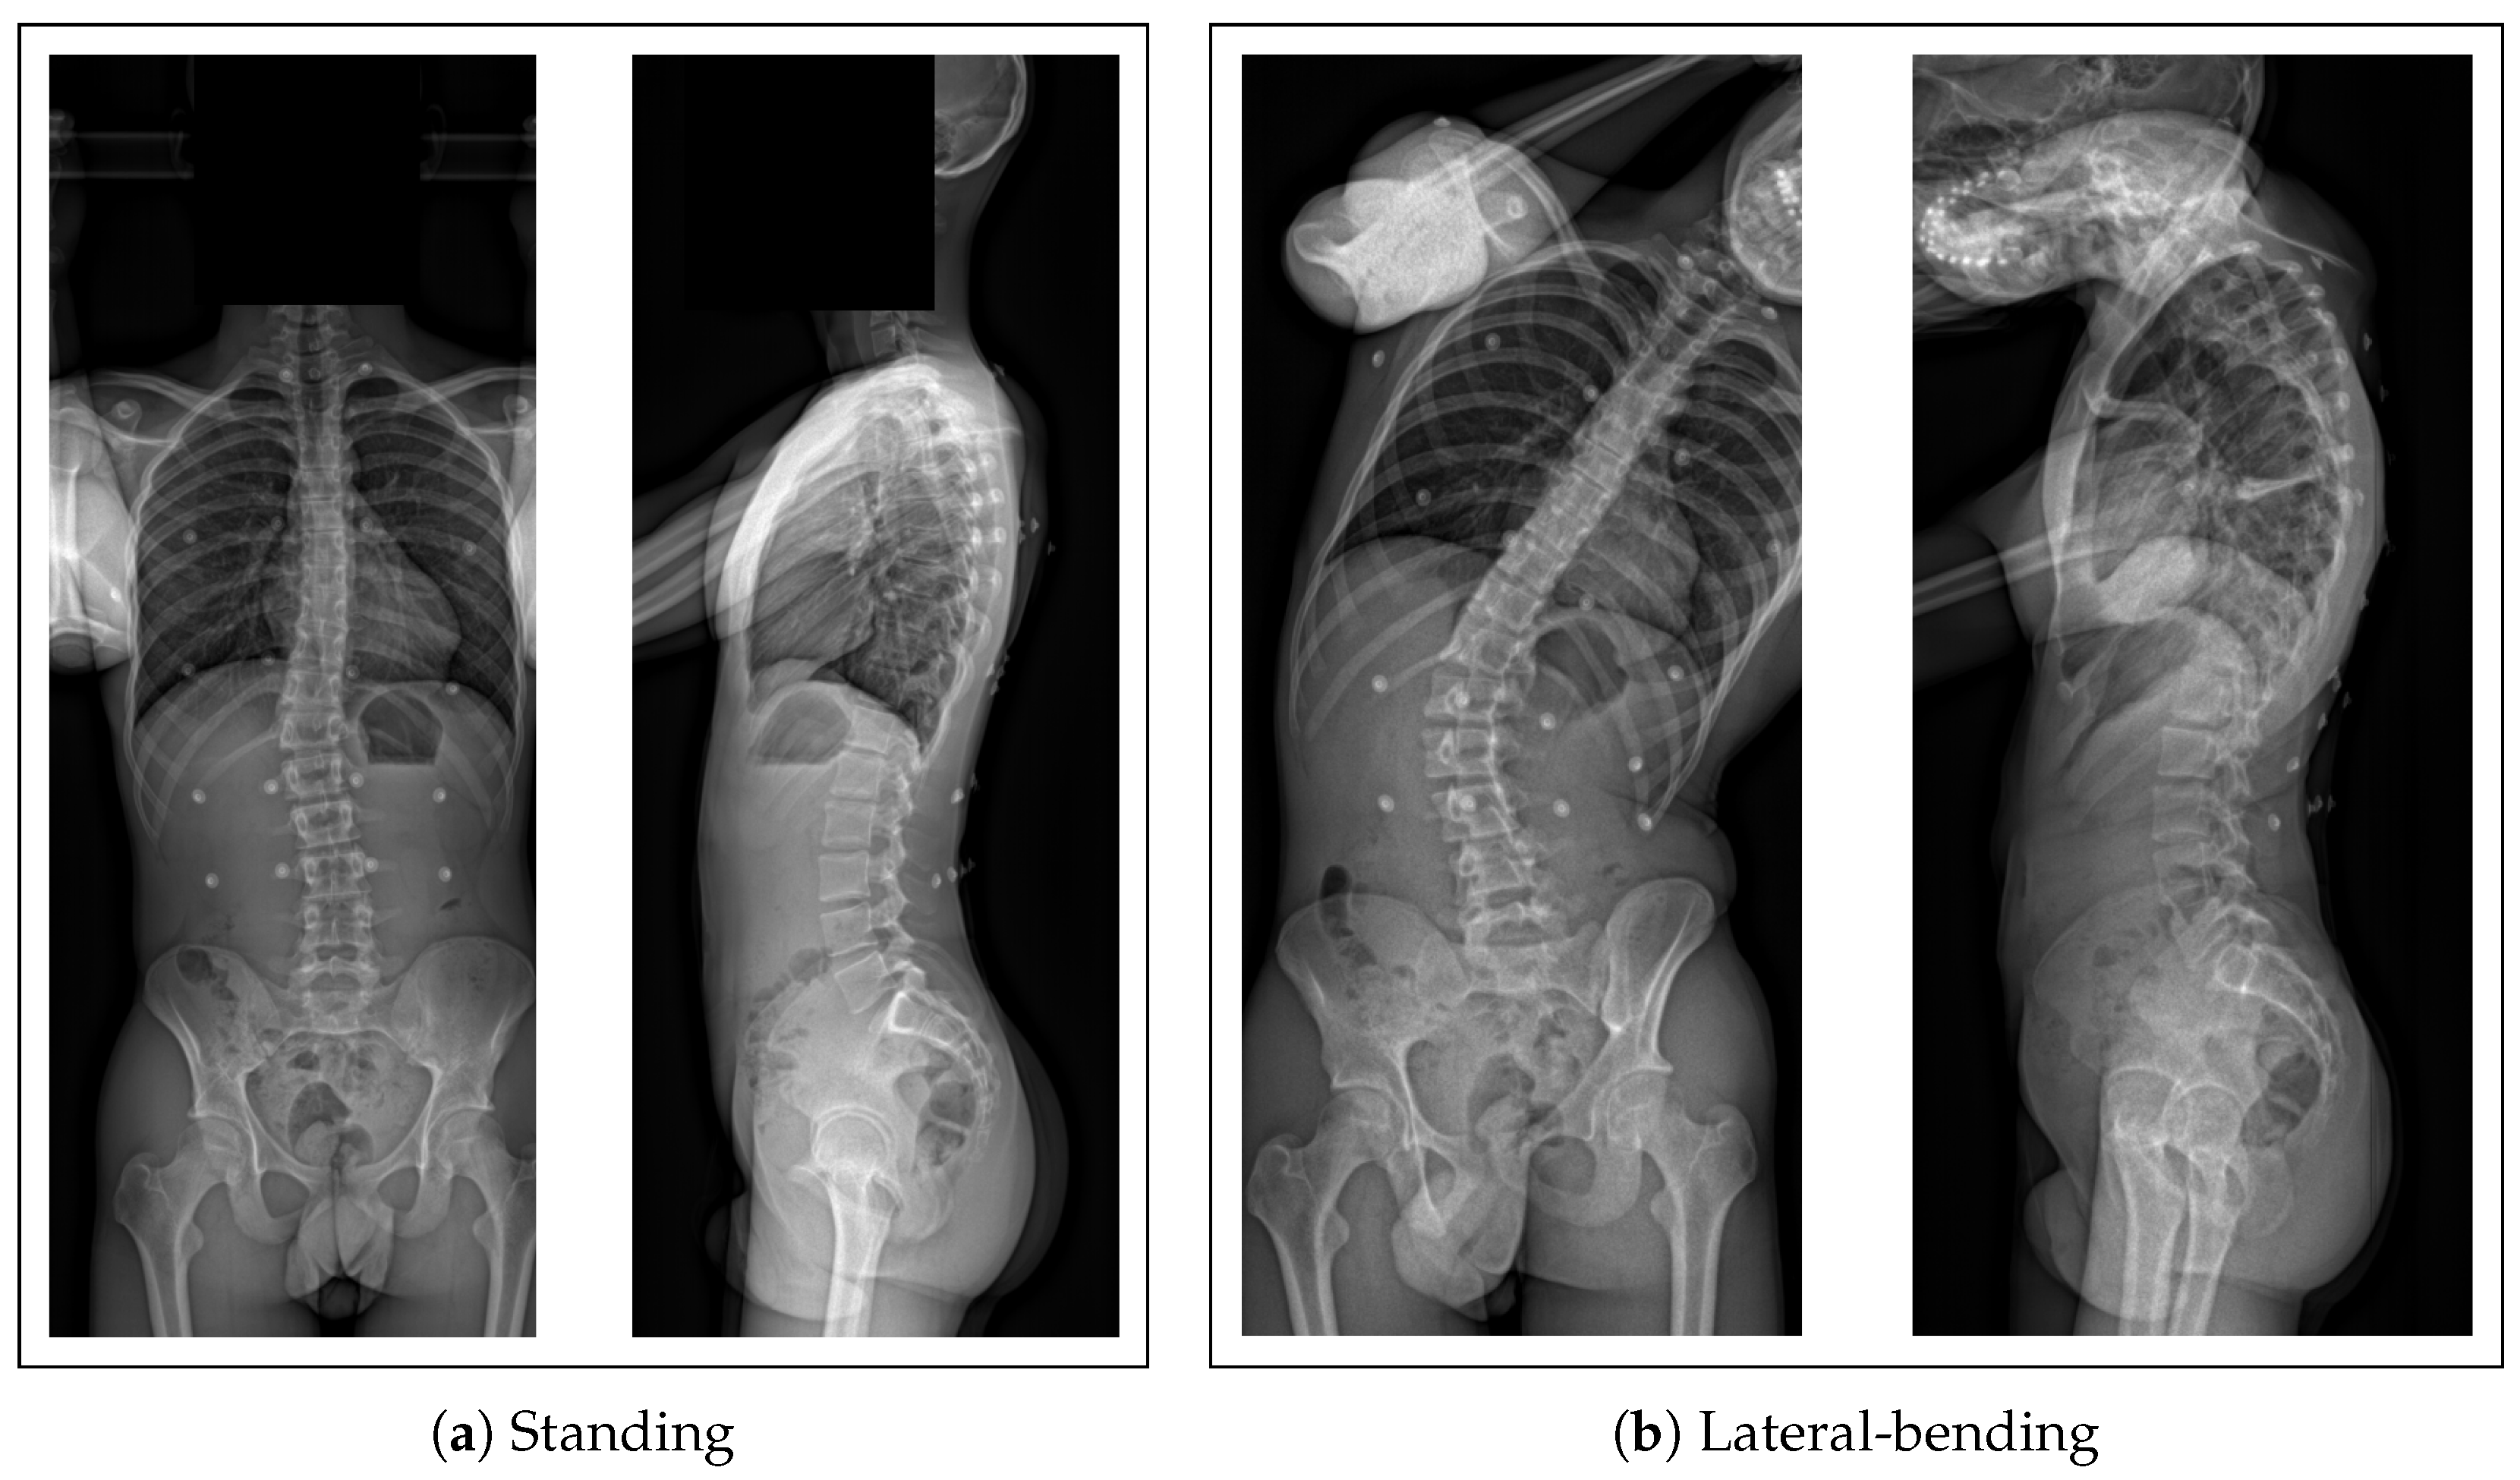

- A biplanar X-ray of their trunk made with an EOS imaging system